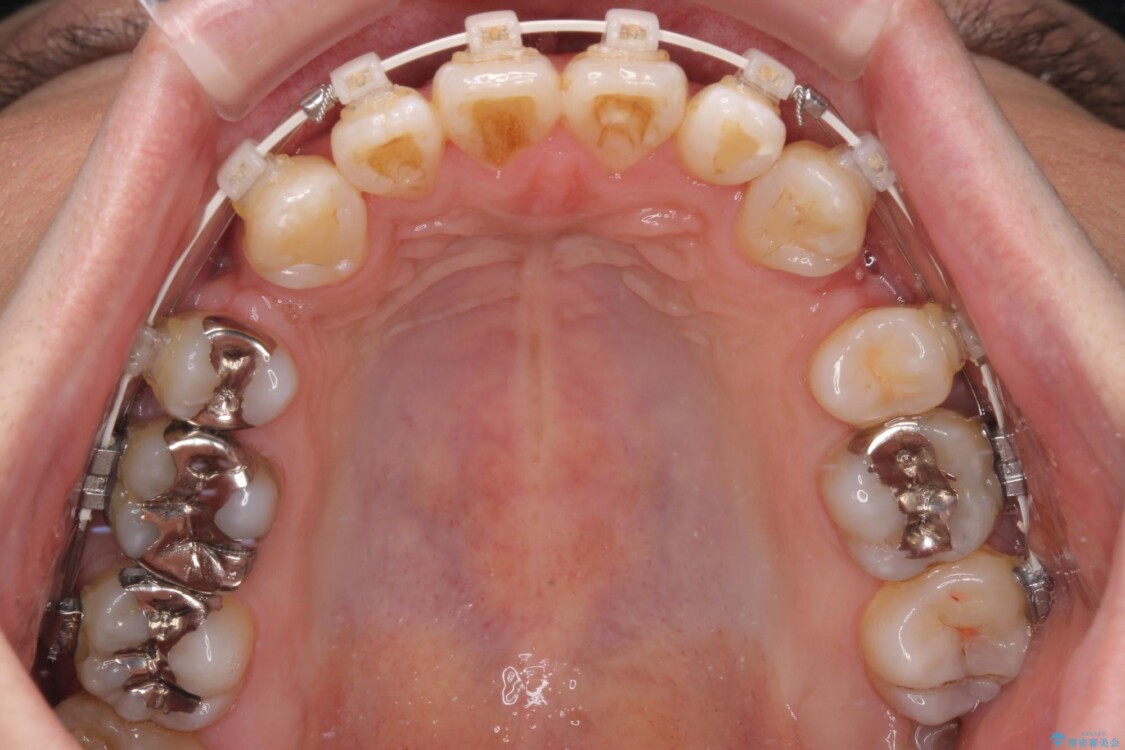

精密検査の結果、上下左右の小臼歯4本を抜歯し、そのスペースに前歯を後方へ移動させる矯正治療をご提案しました。

装置は、透明感のあるクリアブラケットとホワイトコーティングされたワイヤーを使用した、目立ちにくい審美装置を選択。

治療途中

• 口元の突出感を改善!目立ちにくいワイヤー矯正で自信を持てる自然な横顔に 治療途中画像